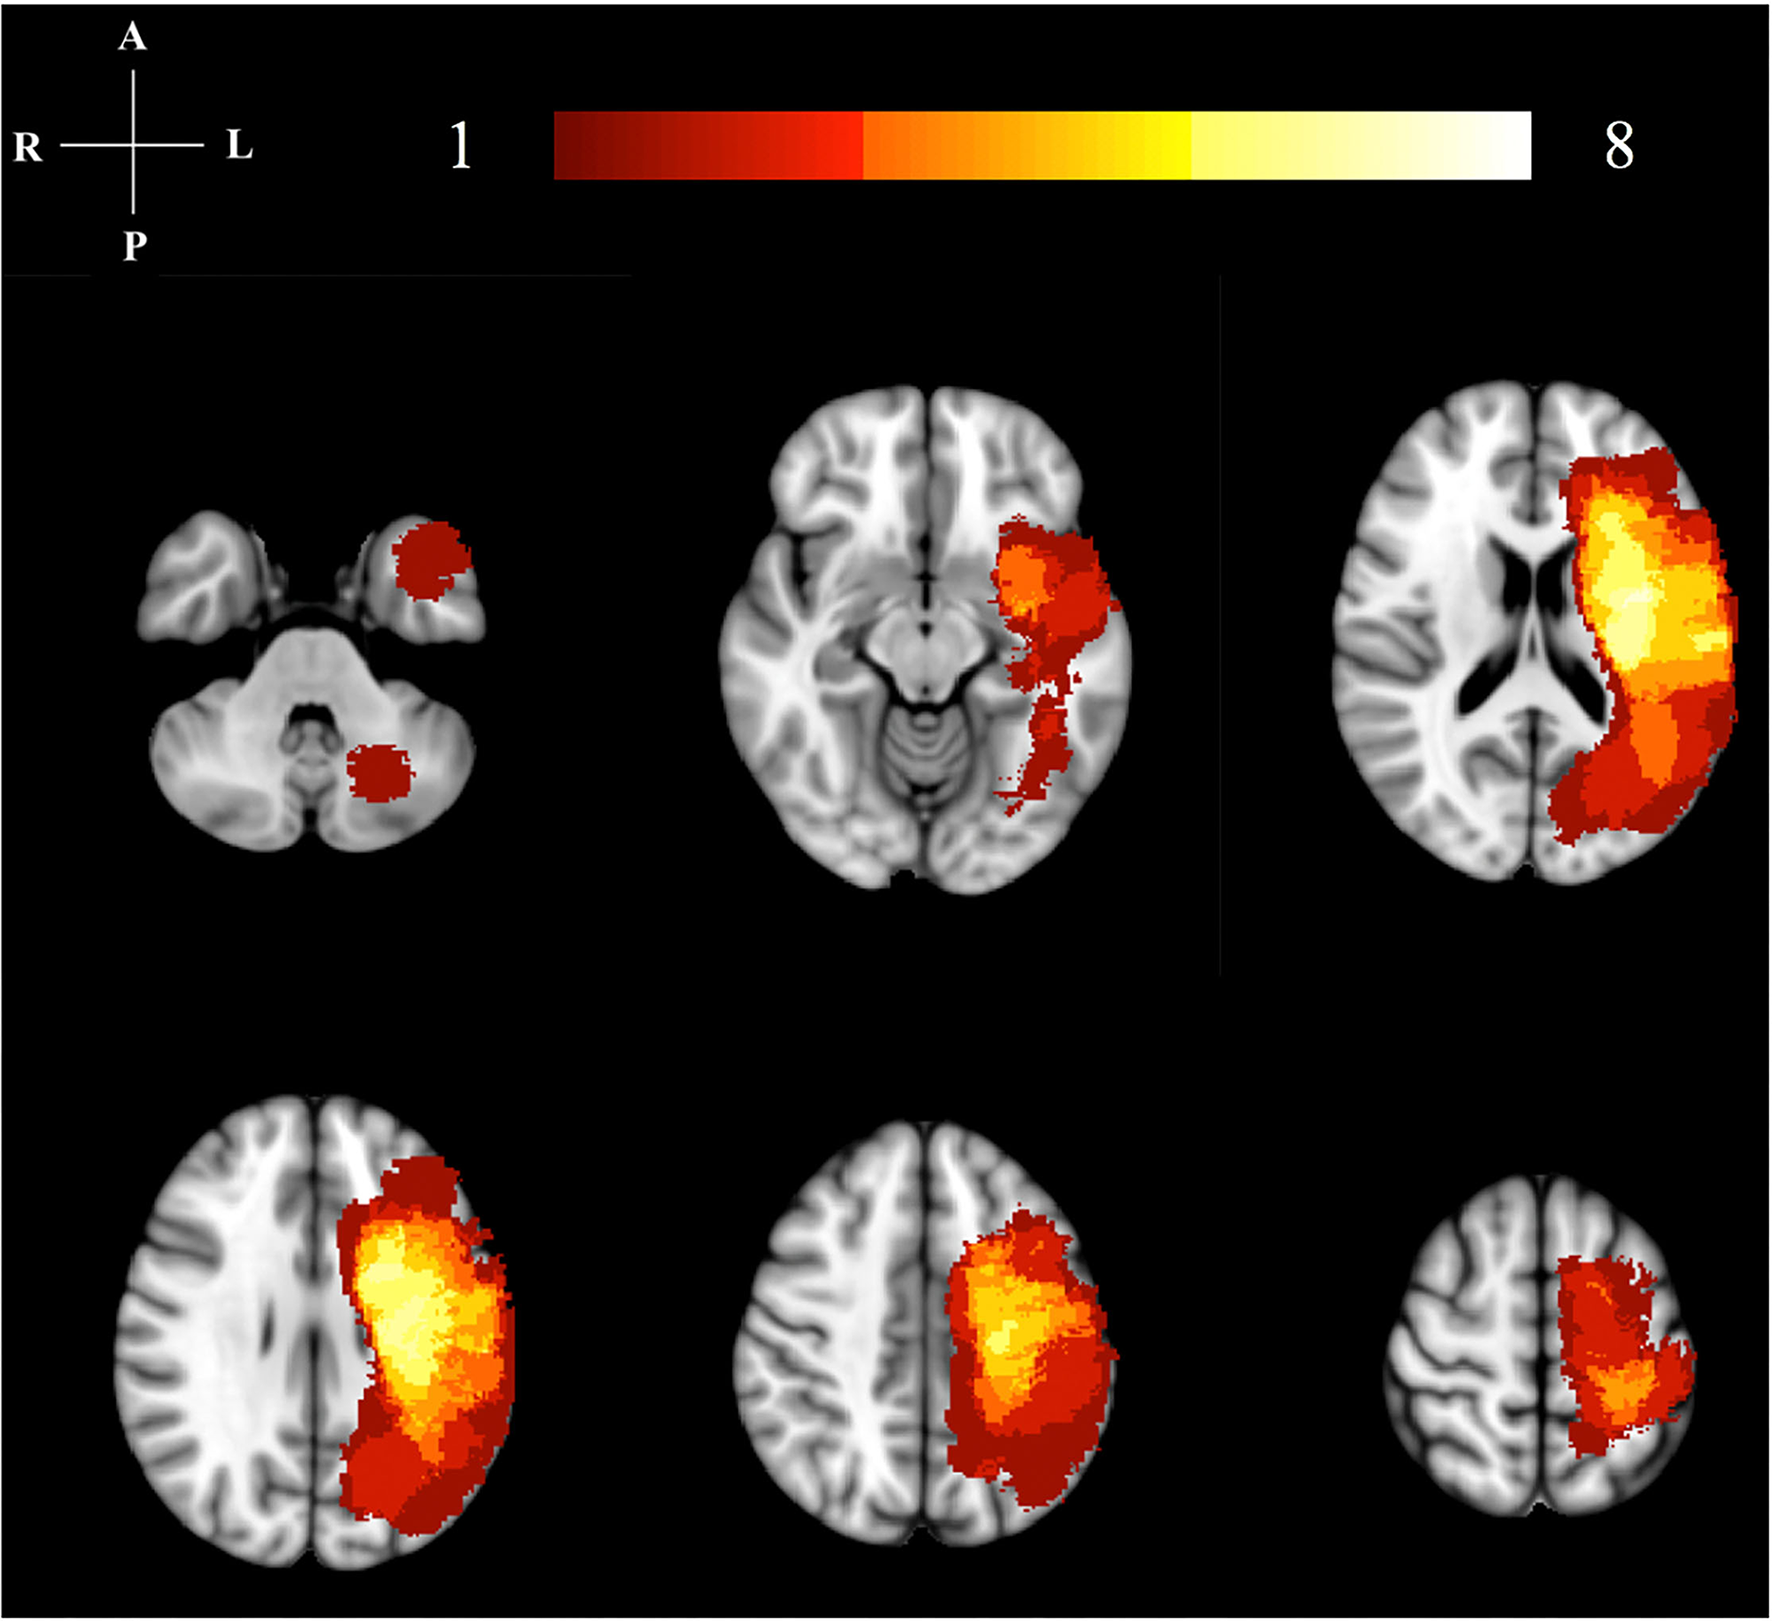

Figure 1

Lesion location map. This image illustrates the lesion distribution for our study. The color bar and numbers represent the number of subjects with a lesion in that area. The highest lesion distribution in shown in bright colors (yellow/white). All right hemisphere lesions have been flipped to the left hemisphere for analysis.